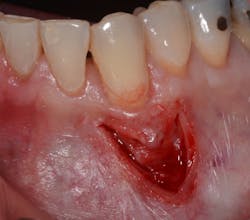

The Bernotti V-Y Flap involves making a submarginal supraperiosteal V-shaped incision 1 mm to 2 mm apical to the mucogingival junction, creating a pedicle flap (figures 2 and 2a). This flap is extended one tooth mesially and distally to the recession defect. It is important to note that the flap should leave the adjacent papillae intact in order to preserve blood supply. An intrasulcular incision is then made with a microsurgical blade to allow for coronal movement of the marginal tissue without tension (figure 3). The root is then scaled/root planed and chemically modified with an amoxicillin slurry for three minutes (figure 3a).